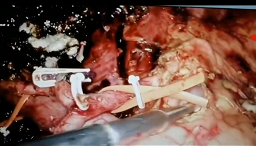

国内领先技术2:腹腔镜III、IV型肝门胆管癌根治术:该项技术系腹部外科领域“天花板”级别手术,在国内应用腔镜技术进行III、IV肝门胆管癌根治手术更是鲜有报道,本中心已常规开展腹腔镜扩大右半肝+全尾叶切除+肝门部淋巴结廓清+肝门胆管重建+胆管空肠吻合术(IIIa型肝门胆管癌);腹腔镜扩大左半肝+全尾叶切除+肝门部淋巴结廓清+肝门胆管重建+胆管空肠吻合术(IIIb型肝门胆管癌);腹腔镜肝中叶切除+全尾叶切除+肝门部淋巴结廓清+肝门胆管重建+胆管空肠吻合术(IV型肝门胆管癌),并取得良好效果。

省内领先技术1:完全腹腔镜胰十二指肠切除术在胆胰恶性肿瘤中应用:胰十二指肠切除术是普外科最复杂的手术之一,而完全腹腔镜胰十二指肠切除术(laparoscopicpancreaticoduodenectomy,LPD)难度更高。该项技术因切除范围较广(切除6个器官)、手术步骤繁琐(需腔镜下完成胰肠吻合、胆肠吻合、胃肠吻合)、学习曲线较长,在国内仅部分中心可常规开展,本中心自2018年4月至今已完成LPD近120例(完成例数省内单中心前三),并在此基础上将胰肠吻合技术进一步改良(“洪式一针法”联合“陈氏缝合技术”的临床应用,大大降低了胰漏发生率。LPD相较于传统开腹胰十二指肠切除术具有手术创伤小、住院时间短、胃肠功能恢复快等优点。